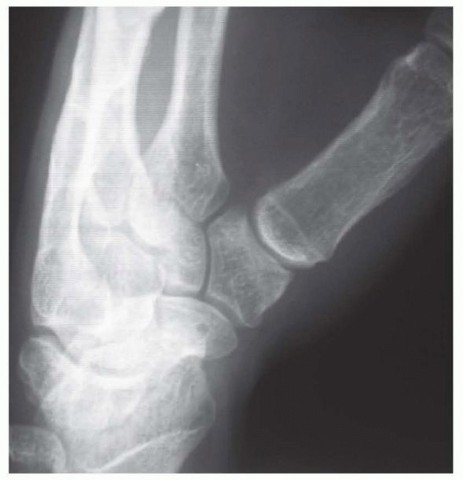

Our imaging protocol must be exhaustive to provide a three-dimensional understanding of the fracture morphology. Standard hand radiographs are insufficient due to the unique 30-degree pronated position of the thumb relative to the rest of the carpus. A True AP View of the Thumb CMC Joint (Robert's view) is obtained with maximal forearm pronation, placing the dorsum of the thumb flat on the cassette. This optimizes visualization of the joint space and the critical ulnar fragment. The True Lateral View (Billing and Gedda) is achieved with the hand pronated 20 degrees and the thumb flat on the cassette, with the X-ray beam tilted 10 degrees from vertical in a distal-to-proximal direction.

Image

For complex, multi-fragmentary Rolando fractures, a Traction View under fluoroscopy is indispensable. Distraction at the CMC joint utilizes ligamentotaxis to help delineate comminuted fragments and assess the potential for closed reduction and percutaneous pinning versus the absolute need for open plating. Furthermore, when plain films inadequately delineate the spatial orientation of fracture fragments, particularly in Zone 2, a high-resolution Computed Tomography (CT) scan is strictly indicated. 3D reconstructions are invaluable for preoperative templating, allowing the surgeon to precisely map screw trajectories and select appropriate plate morphology before entering the operating theater.